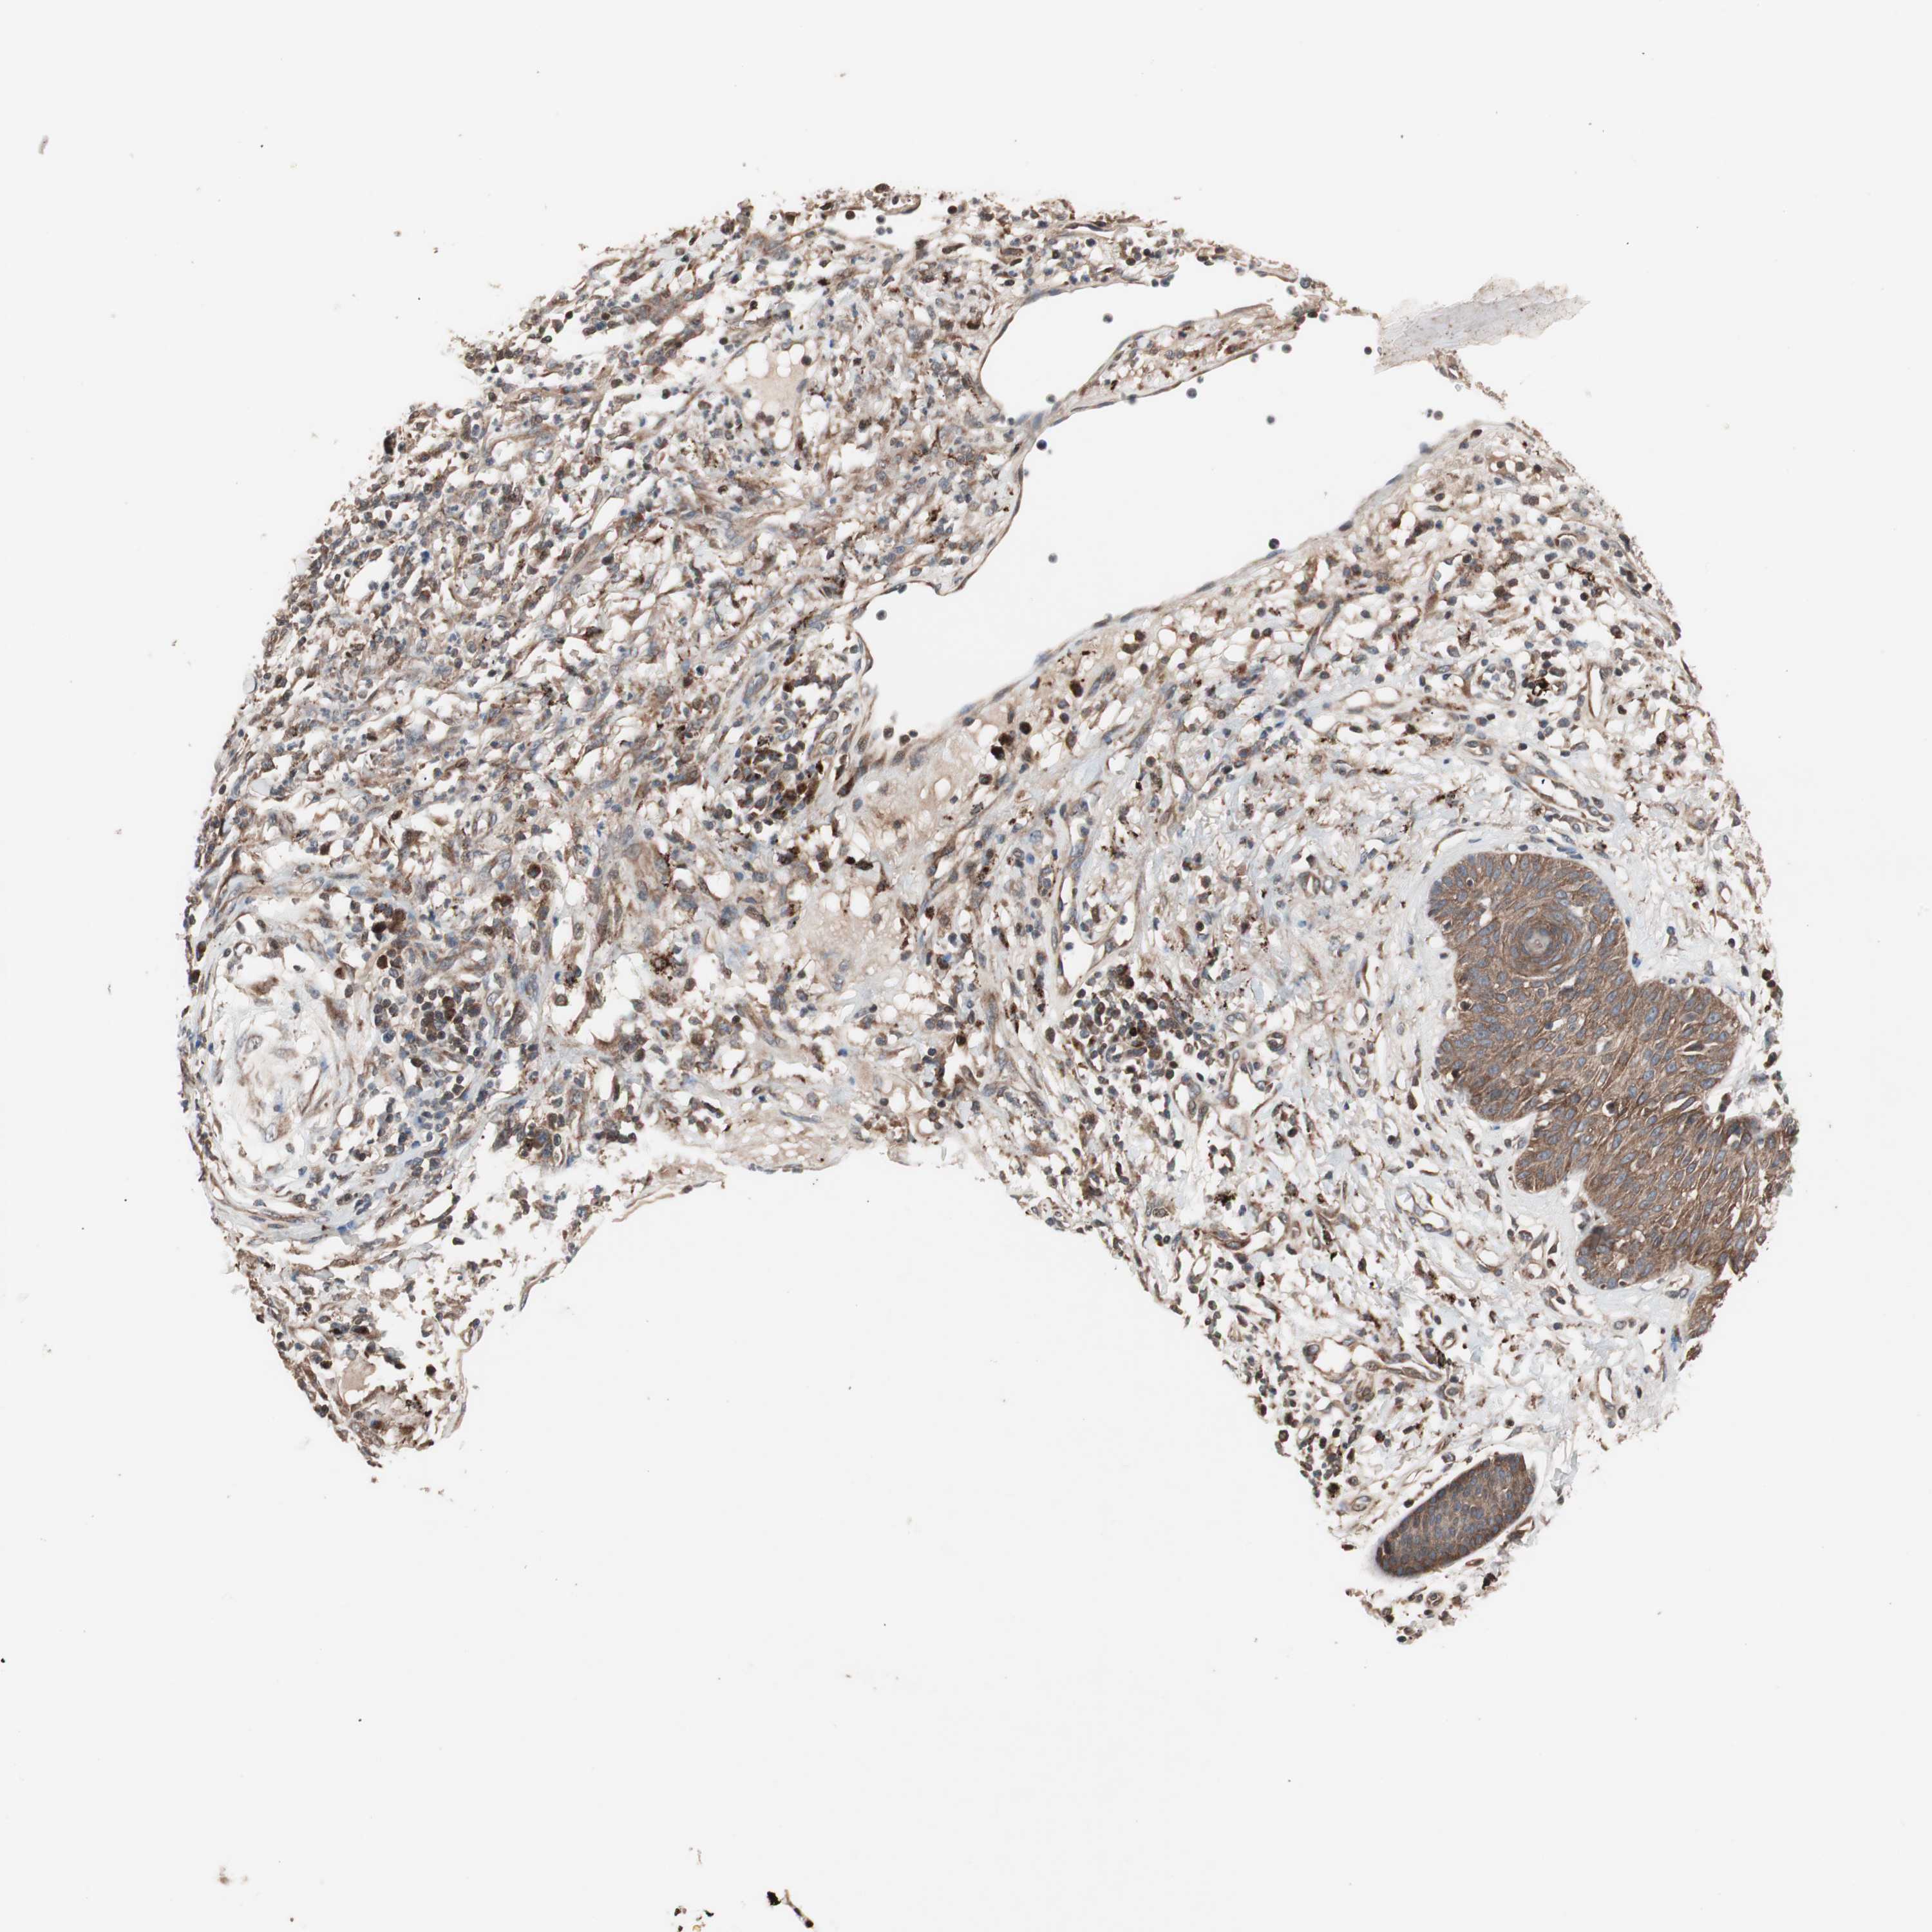

SKIN CANCER - Protein expressioni

A mouse-over function shows sample information and annotation data. Click on an image to view it in a full screen mode. Samples can be filtered based on level of antibody staining by selecting one or several of the following categories: high, medium, low and not detected. The assay and annotation is described here.

Each image is clickable and will lead to virtual microscopy that enables deeper exploration of all samples and also displays staining intensity scores, fraction scores and subcellular localization as well as patient and tissue information for each sample.

Antibody CAB005385

Basal cell carcinoma